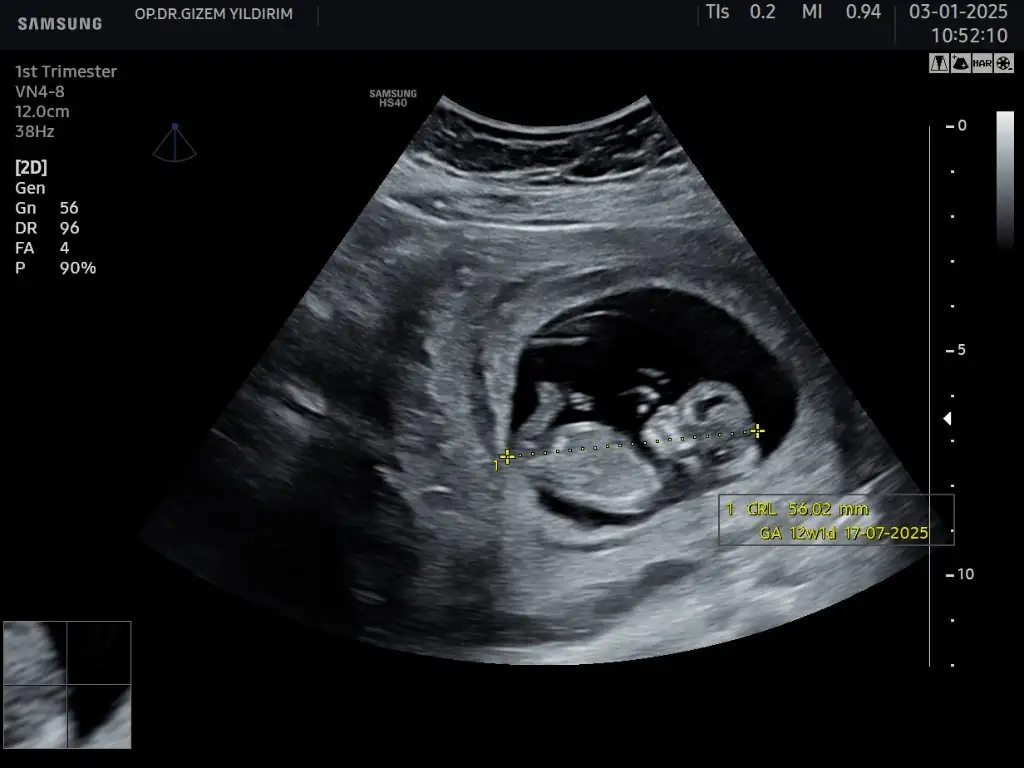

Merhaba kızlar, 11+1 ultrasonuma göre cinsiyet tahmininiz olur mu acaba 🥰

1000042246.webp

1000042250.webp

1000042279.webp